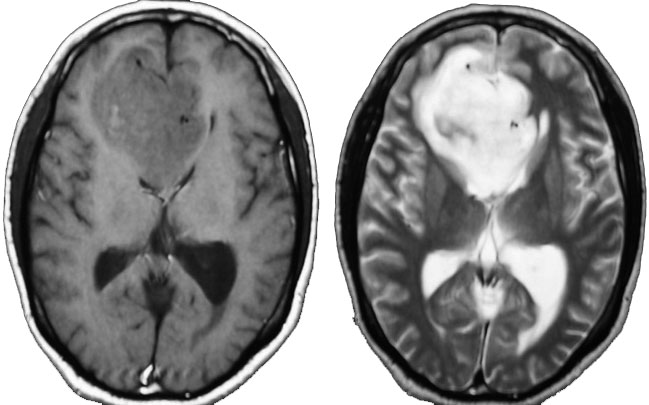

若い成人です,認知機能障害で発症しました。この画像を見るからに悪性神経膠腫,少なくともグレード3のグリオーマであることは明白です。しかし,グレード4膠芽腫あるいはグレード3退形成性星細胞腫にしては腫瘍周辺浮腫が軽すぎます。ですから,グレード3の退形成性乏突起膠腫 AO かも。認知機能の回復と温存を考量して,脳梁損傷と前交連損傷を避けて,右上前頭回と帯状回腫瘍を摘出しました。

左は術後のT1強調ガドリニウム増強像で,残存腫瘍がわかります。この腫瘍に対してICE (IFO/CDDP/VP-16) 化学療法を1コースしました。右側のMRIが1ヶ月後の画像です。このように1p/19q欠失のある退形成性乏突起膠腫は,化学療法感受性がとても高い悪性グリオーマです。ですから,手術で後遺症を残さないように,勢い込んで腫瘍を摘出しようとしないことが大切です。光顕診断はAOで,後々の解析で1p/19q codeletion でした。